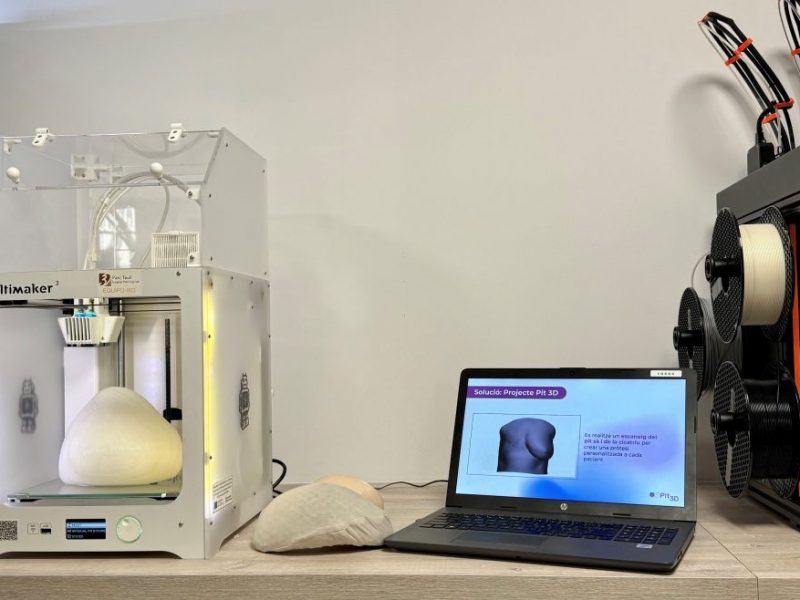

El Parc Taulí ha iniciat un assaig clínic multicèntric, aleatoritzat i prospectiu per avaluar l’impacte clínic i econòmic de la cirurgia digital 3D en l’àmbit de la traumatologia i la cirurgia ortopèdica. L’objectiu principal és demostrar que la planificació virtual combinada amb la impressió 3D d’instrumental quirúrgic personalitzat no només aporta beneficis al pacient, sinó que també redueix temps i estalvia recursos al centre mèdic respecte a la cirurgia convencional.

L’evidència científica suggereix que la tecnologia 3D, a partir de planificacions exhaustives, implants a mida i guies quirúrgiques personalitzades, pot millorar considerablement aquests processos quirúrgics”, apunta Xavier Garcia, biotecnòleg i coordinador d’assaigs clínics i projectes d’R+D+I del Laboratori 3D del Parc Taulí.

L’assaig clínic s’emmarca dins del 3DAdopt, un projecte transformador desenvolupat pel Parc Taulí i finançat pel Servei Català de Salut que busca generar evidència per escalar la cirurgia digital 3D al sistema públic de salut.

Procés per tractar l’artroplàstia de maluc amb cirurgia digital 3D, des de la planificació digital 3D a la impressió 3D per crear un producte sanitari personalitzat.

En aquest sentit, segons afirma Fillat, la tecnologia 3D ha guanyat pes, especialment en cirurgia ortopèdica i traumatologia, perquè “permet crear models anatòmics exactes i guies quirúrgiques personalitzades a partir de les imatges del pacient, i simular digitalment el procediment quirúrgic, millorant la precisió i reduint els marges d’error”.